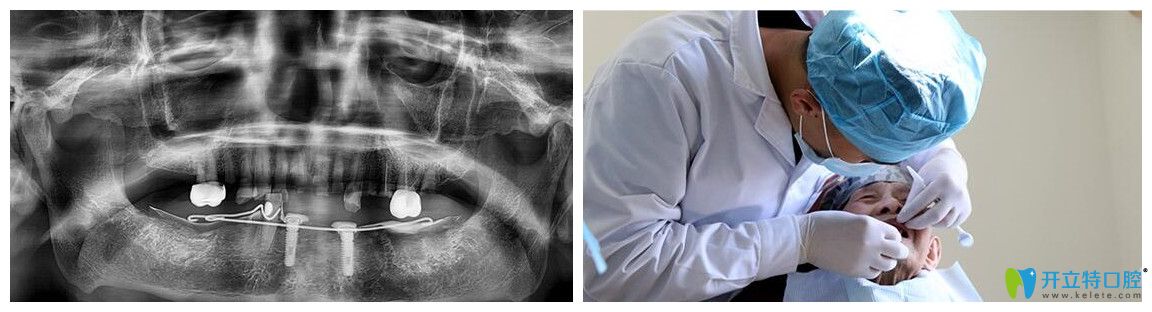

醫(yī)護(hù)人員為其量血壓、測(cè)血糖。檢查設(shè)計(jì)種植方案,通過(guò)評(píng)估情況,包括上下頜咬合關(guān)系、牙槽骨(厚度、密度、高度、X片、CT評(píng)估)、牙周健康情況、全身有無(wú)系統(tǒng)疾病等,后來(lái)確定韓老的情況符合種植牙的手術(shù)條件。

侯主任為韓老實(shí)施精準(zhǔn)種植手術(shù)圖

術(shù)前,醫(yī)護(hù)人員為韓老又進(jìn)行了一遍CT口腔檢查。侯國(guó)鎮(zhèn)主任用“高齡精準(zhǔn)種”技術(shù)為韓老實(shí)施精準(zhǔn)種植手術(shù)。但在韓老進(jìn)到手術(shù)室的時(shí)候,主任察覺(jué)到了韓老的緊張感,悄悄鼓勵(lì)他:“放輕松,相信我,治療過(guò)程很快的,而且也不會(huì)有太大的疼痛?!痹谥魅蔚囊龑?dǎo)下,韓老狀態(tài)很放松,手術(shù)也很順利的完成了。?

韓老拍CT和醫(yī)生檢查的圖片

術(shù)后CT片顯示,韓老口內(nèi)的種植體植入非常周正、位置和導(dǎo)板設(shè)計(jì)完全吻合,手術(shù)非常成功。王明霞醫(yī)生正在給韓老佩戴牙冠修復(fù)體。